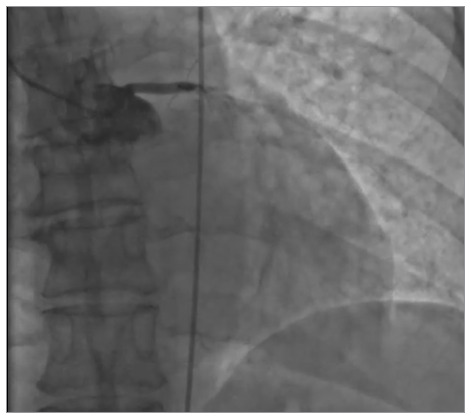

Left main occlusion presenting as ST-segment elevation myocardial infarction is an exceedingly morbid condition. This article reports a case of cardiac arrest in a patient after a treadmill stress test. Coronary angiography revealed 100% occlusion of the left main coronary artery. Left ventricular unloading with the Impella CP heart pump (ABIOMED/Johnson & Johnson MedTech) was used, after which epicardial blood flow was restored without angioplasty. The patient underwent surgical revascularization. Despite a prolonged revascularization time, there was no evidence of severe myocardial injury postoperatively.